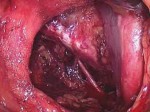

Um estudo feito pela Universidade do Missouri, nos EUA, sobre a segurança do medicamento finasterida aponta que a droga pode reduzir em 30% o risco de câncer de próstata – glândula do sistema reprodutor masculino, do tamanho de uma castanha, que produz parte do sêmen. Os resultados também sugerem que o remédio não aumenta as mortes por uma forma agressiva da doença, como concluíram pesquisas anteriores.Segundo os autores, liderados por Michael LeFevre, esse trabalho pode levar a uma nova perspectiva sobre o uso do medicamento para prevenção do câncer de próstata. Na opinião dos especialistas, a finasterida poderia evitar milhares de casos por ano, além de poupar muitos homens de tratamentos com efeitos colaterais desagradáveis.

Em altas doses, o remédio é indicado para tratar o aumento da próstata (chamada hiperplasia benigna, que leva a problemas urinários) ou o câncer. Já, em baixas dosagens, é recomendado para a calvície.

Há 18 anos, cientistas haviam verificado que a finasterida poderia diminuir o risco de câncer de próstata, mas também havia sido detectado um pequeno aumento de tumores agressivos entre os usuários. De acordo com alguns pesquisadores, porém, a droga não causava esses tipos de câncer, apenas fazia com que eles ficassem mais fáceis de ser detectados em uma biópsia.

Apesar disso, essa preocupação levou a agência Food and Drug Administration (FDA), que regula alimentos e remédios nos EUA, a rejeitar a finasterida para prevenção do câncer de próstata, incluindo avisos nas embalagens dos produtos.